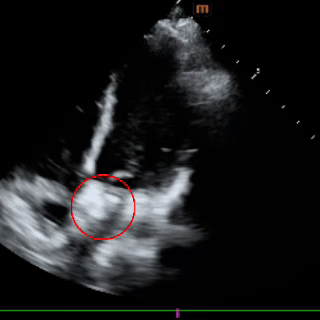

术前超声

超声所见:

1、各房室腔内径正常,大动脉内径及位置关系正常。

2、室间隔及左室后壁厚度及运动幅度正常。多切面显示房间隔中部可见宽约5mm的回声失落,多普勒示左向右分流束,流速约122cm/s,室间隔连续。

3、CDFI示三尖瓣见少量反流,流速约275cm/s,估测肺动脉收缩压约35mmHg;二尖瓣见少量反流,反流面积约1.0cm2;肺动脉瓣见小反流束。

4、心包厚度正常,心包腔内未见液性暗区。

5、心功能测值正常。

超声提示:房间隔中部回声失落,考虑:房间隔缺损;三尖瓣、二尖瓣少量反流;肺动脉轻度高压。